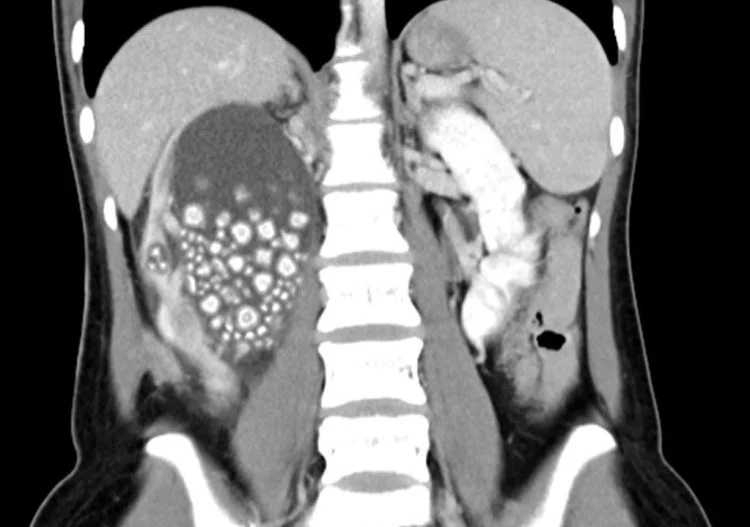

Μία 20χρονη παραπονιόταν για έντονο πόνο στο κάτω μέρος της πλάτης της και οι γιατροί που την εξέτασαν, βρήκαν 300 μικρές πέτρες στο νεφρό της.Ειδικότερα, η γυναίκα από την Ταϊβάν υποβλήθηκε πρόσφατα σε χειρουργική επέμβαση, προκειμένου να αφαιρεθούν 300 μικροί λίθοι από το δεξί της νεφρό.

Η νεαρή εισήχθη σε νοσοκομείο της πόλης Taina, αφού εκτός από έντονο πόνο, είχε πυρετό και μια εξέταση αίματος έδειξε ασυνήθιστα υψηλό αριθμό λευκών αιμοσφαιρίων.Μετά την αξονική τομογραφία, διαπιστώθηκε ότι το δεξί νεφρό της Yu ήταν γεμάτο πέτρες και η πρώτη ενέργειά των γιατρών ήταν να χορηγηθούν στη νεαρή γυναίκα αντιβιοτικά, ενώ στη συνέχεια αφαίρεσαν του εκατοντάδες λίθους.

Τελικά, οι γιατροί αφαίρεσαν πάνω από 300 πέτρες, μεγέθους μεταξύ 5 και 2 εκατοστών, με την ασθενή να τους ενημερώνει ότι δεν έπινε σχεδόν καθόλου νερό και προτιμούσε τα ζαχαρούχα τσάγια και χυμούς για ενυδάτωση, με αποτέλεσμα αυτό της προκάλεσε χρόνια αφυδάτωση.